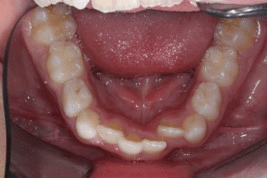

image25 Settembre 2025 by Studio Dentistico ZemellaArticoli correlati:ORTOGNATODONZIA risolta con la tecnica di ortopedia…ORTOGNATODONZIA risolta con tecnica multi bracketORTOGNATODONZIA risolta con mascherine…Conservativa - "Otturazioni"Endodonzia - "Devitalizzazioni"Chirurgia Orale e Implantologia